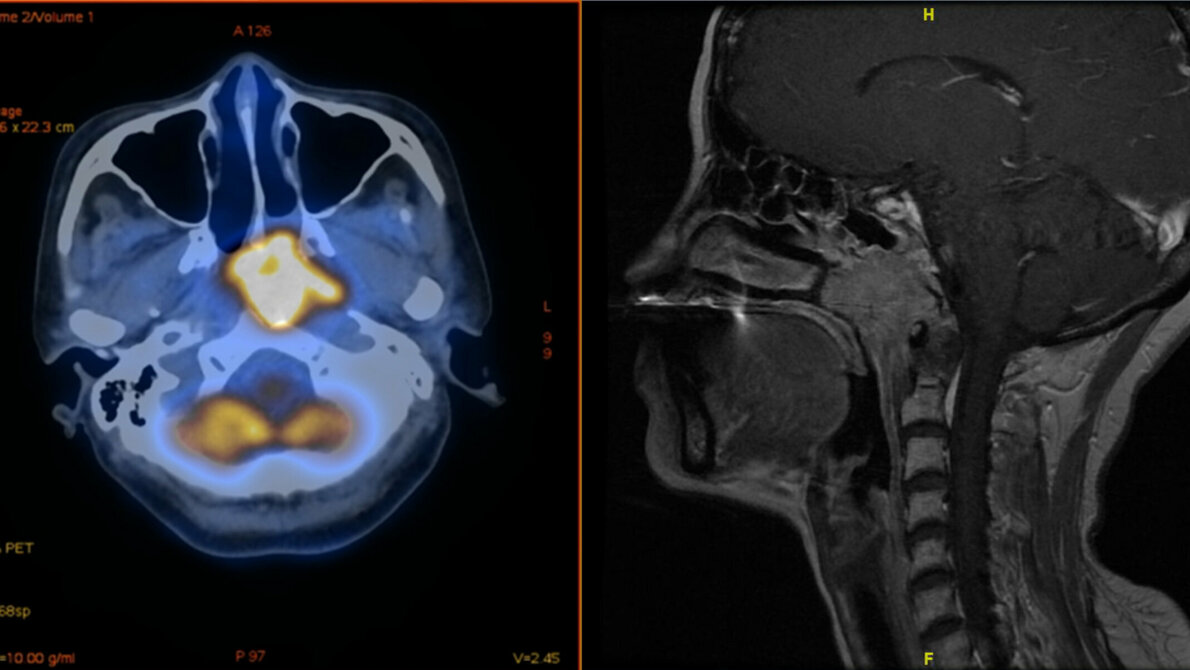

Viele Krebszellen sind dazu in der Lage, die Immunantwort des Körpers zu unterlaufen. Sie betätigen dazu eine Art Knopf auf den Immunzellen, den PD-1-Rezeptor. Dadurch schalten sie diese körpereigenen Abwehrtruppen gewissermaßen ab. Mit Medikamenten lassen sich die PD-1-Rezeptoren blockieren. Das Immunsystem kann so den Tumor besser bekämpfen. Bei der Impfung gegen Covid wird ebenfalls die Immunantwort stimuliert, wobei der PD-1-Rezeptor involviert ist. „Man befürchtete, dass die Impfung sich nicht mit einer Anti-PD-1-Therapie vertragen könnte“, erklärt Dr. Jian Li vom Institut für Molekulare Medizin und Experimentelle Immunologie (IMMEI) am Universitätsklinikum Bonn. „Diese Gefahr besteht insbesondere bei Nasenrachenkrebs, der genau wie das SARS-Cov-2-Virus die oberen Atemwege befällt.“

Nasenrachenkrebs ist hierzulande recht selten. In Südchina und anderen Ländern Südostasiens ist die Erkrankung dagegen weit verbreitet. Als Gründe vermutet man unter anderem den häufigen Einsatz von Klimaanlagen in den feuchten und heißen Regionen. Auch Ernährungsfaktoren scheinen eine wichtige Rolle zu spielen. In Taiwan gilt Nasenrachenkrebs inzwischen bei jungen Männern als eine der häufigsten Todesursachen.